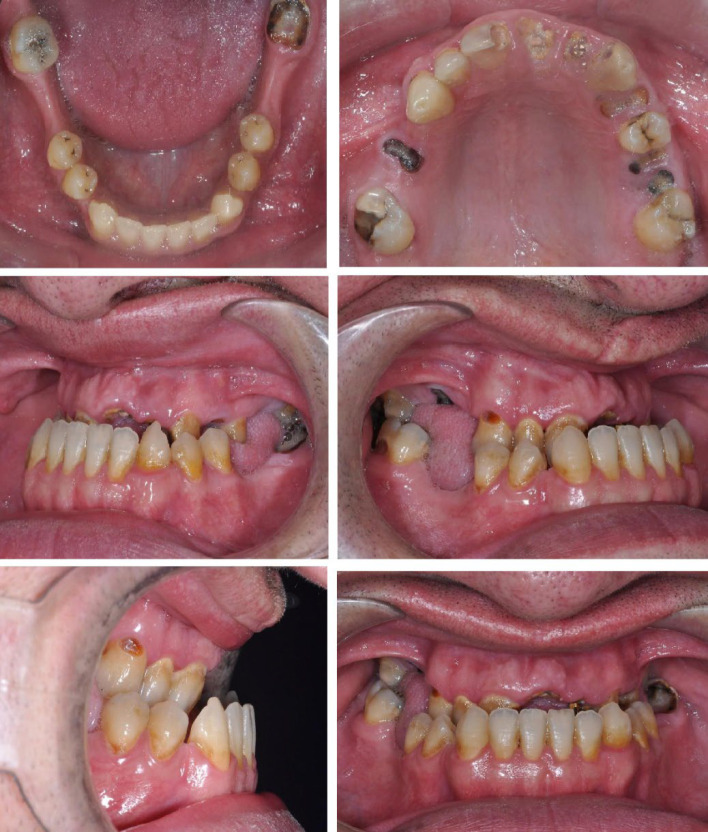

正颌手术是治疗面部美学和咬合问题患者的关键治疗方法,传统上包括术前正畸,手术和术后正畸治疗。然而,常规方法持续时间的延长往往导致患者的不满。作为回应,手术优先的方法(SFA)已经成为一种替代方案,旨在简化治疗并减少复杂性。本病例报告探讨了SFA在术前不进行正畸的情况下的实施,重点是其与上颌间固定(IMF)螺钉的整合。一个25岁的男性表现为严重的下颌后颌和面部不对称。放射学评估证实了骨骼差异,促使手术解决。利用三维规划软件,对LeFort I型上颌前进截骨术和双侧矢状劈开截骨术进行了规划。术中策略性放置IMF螺钉以稳定上颌骨下颌复合体。立即矫正术后调整-启动牙列对齐和水平。定期随访,确保治疗进展及稳定。在手术优先入路中使用IMF螺钉有助于精确的手术动作,加快治疗时间,并提高患者舒适度。这种辅助技术代表了一个有前途的途径,以提高手术精度和病人的结果,在正颌手术。需要进一步的研究来探索这种方法在不同患者群体中的长期稳定性和更广泛的适用性。

Orthognathic surgery, a pivotal treatment for patients with significant facial aesthetic and occlusal concerns, traditionally involves a phased approach comprising preoperative orthodontics, surgery, and postoperative orthodontic treatment. However, the extended duration of conventional methods often leads to patient dissatisfaction. In response, the surgery-first approach (SFA) has emerged as an alternative, aiming to streamline treatment and reduce complexity. This case report explores the implementation of the SFA without preoperative orthodontics, focusing on its integration with intermaxillary fixation (IMF) screws. A 25-year-old male presented with severe mandibular retrognathia and facial asymmetry. The radiographic evaluation confirmed the skeletal discrepancy, prompting a surgical solution. Utilizing three-dimensional (3D) planning software, LeFort I osteotomy for maxillary advancement and bilateral sagittal split osteotomy (BSSO) for mandibular setback was planned. IMF screws were strategically placed to stabilize the maxillomandibular complex intraoperatively. Immediate postoperative orthodontic adjustments-initiated dentition alignment and leveling. Regular follow-up ensured treatment progress and stability. The use of IMF screws in the surgery-first approach facilitated precise surgical movements, accelerated treatment timelines, and enhanced patient comfort. This adjunctive technique represents a promising avenue for improving surgical precision and patient outcomes in orthognathic surgery. Further research is warranted to explore the long-term stability and broader applicability of this approach across diverse patient populations.